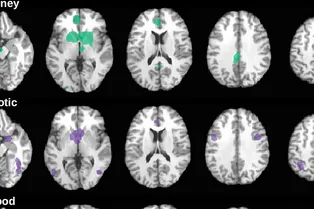

За удовольствие от эротики, сладкого и денег отвечают разные структуры мозга